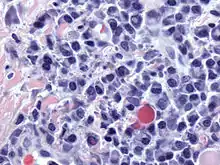

Dutcher body (plural Dutcher bodies)

- (microbiology) One of the periodic acid-Schiff reaction-positive nuclear inclusions, containing immunoglobulin, that are either invaginated into or overlying the nucleus.